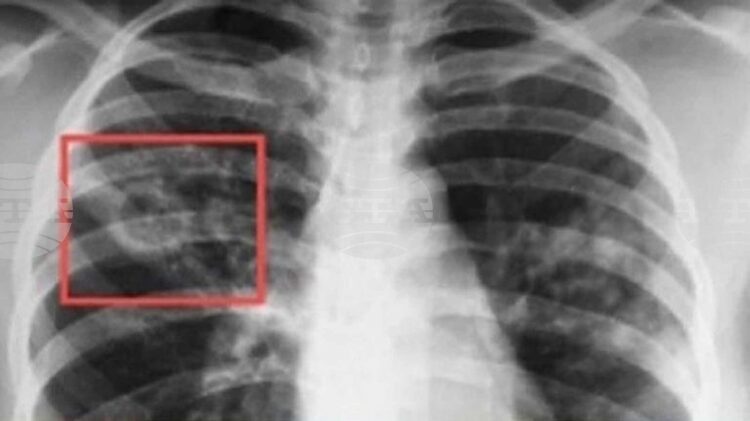

Безплатни прегледи за риск от туберкулоза в Плевен от 23 до 26 септември в болница „Д-р Георги Странски“_68c9053516ebb.jpeg